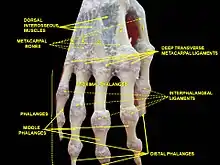

Joint structure

The PIP joint exhibits great lateral stability. Its transverse diameter is greater than its antero-posterior diameter and its thick collateral ligaments are tight in all positions during flexion, contrary to those in the metacarpophalangeal joint.[1]

At the level of the PIP joint the extensor mechanism splits into three bands. The central slip attaches to the dorsal tubercle of the middle phalanx near the PIP joint. The pair of lateral bands, to which contribute the extensor tendons, continue past the PIP joint dorsally to the joint axis. These three bands are united by a transverse retinacular ligament, which runs from the palmar border of the lateral band to the flexor sheath at the level of the joint and which prevents dorsal displacement of that lateral band. On the palmar side of the joint axis of motion, lies the oblique retinacular ligament [of Landsmeer] which stretches from the flexor sheath over the proximal phalanx to the terminal extensor tendon. In extension, the oblique ligament prevents passive DIP flexion and PIP hyperextension as it tightens and pulls the terminal extensor tendon proximally.[2]

Palmar structures

In contrast, on the palmar side, a thick ligament prevents hyperextension. The distal part of the palmar ligament, called the palmar plate, is 2 to 3 millimetres (0.079 to 0.118 in) thick and has a fibrocartilaginous structure. The presence of chondroitin and keratan sulfate in the dorsal and palmar plates is important in resisting compression forces against the condyles of the proximal phalanx. Together these structures protect the tendons passing in front and behind the joint. These tendons can sustain traction forces thanks to their collagen fibers.[1]

Palmar ligament

The palmar ligament is thinner and more flexible in its central-proximal part. On both sides it is reinforced by the so-called check rein ligaments. The accessory collateral ligaments (ACL) originate at the proximal phalanx and are inserted distally at the base of the middle phalanx below the collateral ligaments.[1]

The accessory ligament and the proximal margin of the palmar plate are flexible and fold back upon themselves during flexion. The flexor tendon sheaths are firmly attached to the proximal and middle phalanges by annular pulleys A2 and A4, while the A3 pulley and the proximal fibres of the C1 ligament attach the sheaths to the mobile volar ligament at the PIP joint. During flexion this arrangement produces a space at the neck of the proximal phalanx which is filled by the folding palmar plate.[2]

The palmar plate is supported by a ligament on either side of the joint called the collateral ligaments, which prevent deviation of the joint from side to side. The ligaments can partially or fully tear and can avulse with a small fracture fragment when the finger is forced backwards into hyperextension. This is called a "palmar plate, or volar plate injury".[3]

The palmar plate forms a semi-rigid floor and the collateral ligaments the walls in a mobile box which moves together with the distal part of the joint and provides stability to the joint during its entire range of motion. Because the palmar plate adheres to the flexor digitorum superficialis near the distal attachment of the muscle, it also increases the moment of flexor action. In the PIP joint, extension is more limited because of the two so called check-rein ligaments, which attach the palmar plate to the proximal phalanx.[2]